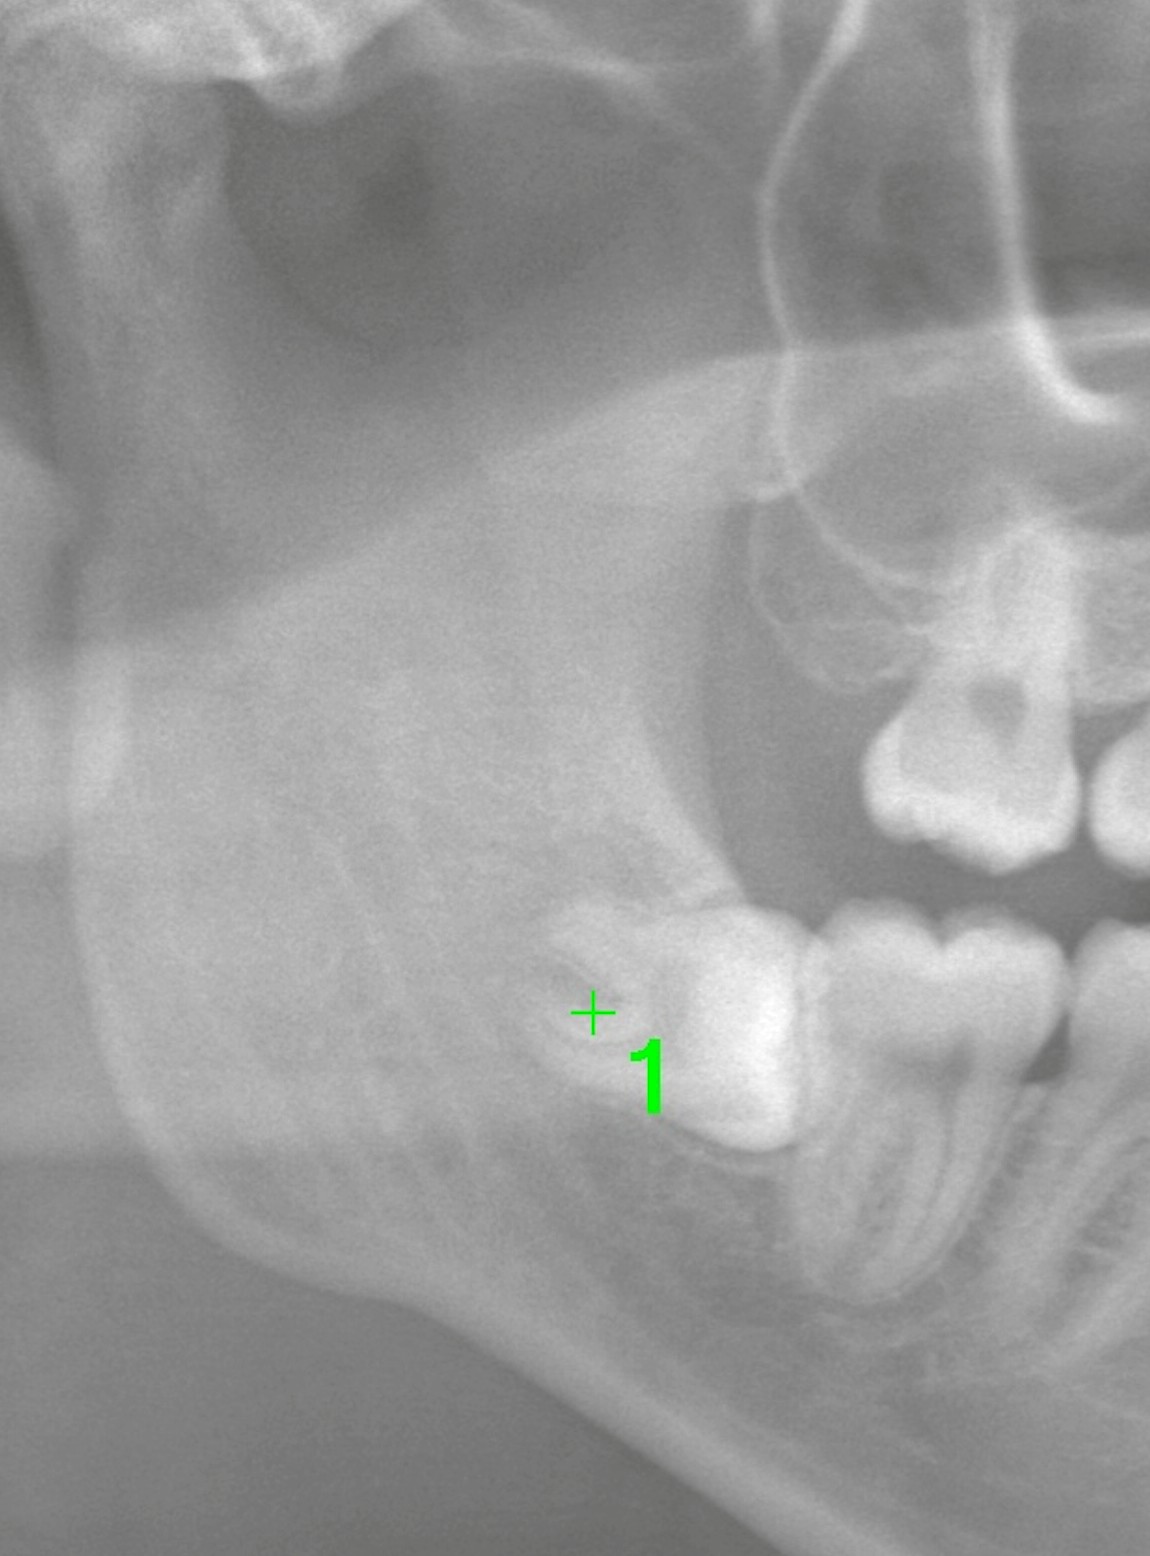

2Dのパノラマ写真

真横に水平埋伏している親知らずであることがわかります。

歯根は2根あり、2D画像上では確かに下歯槽神経に近接しているように見えます。

このようなケースでは、CTを撮影し、三次元的に歯と神経の位置関係を正確に把握することが重要になります。